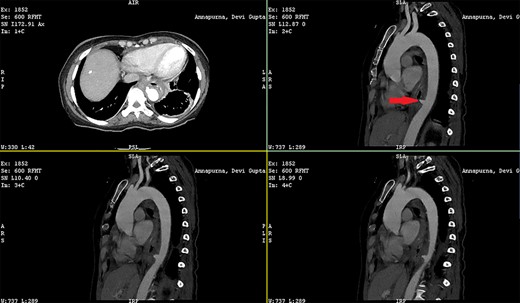

Patient 1: a 52-year-old woman, non-diabetic, non-hypertensive, was referred to the emergency with a history of large-volume, frank hematemesis (four episodes in 3 days). Positive history included recurrent cough for the past 1 year and low-grade fever for 3 months. No history of dysphagia, jaundice, abdominal distension, pain abdomen or altered sensorium. No history of chronic medications (oral anticoagulants or anti-platelets), analgesic intake or any substance abuse. She had received four units of packed red cells at an outside facility prior to admission. She was conscious, oriented, hemodynamically labile (heart rate: 110/min; BP: 86/60 mm Hg) with mild fever (99°F). General survey revealed obvious pallor. All other system examinations were within acceptable limits. Her hemoglobin (Hb) was 7.3 gram%, total leukocyte count (TLC) was 6400 cells/mm3, total bilirubin was 1.31 mg/dl and total protein was 4.75 gram%. An urgent UGI endoscopy revealed an opening in the posterior wall of the lower third of the esophagus, with a diverticulum. Inflammatory changes were noted in the diverticulum (Fig. 1). Contrast-enhanced computed tomogram (CECT) revealed erosion of the pouch into the thoracic aorta (Fig. 2), and a diagnosis of AEF with acute UGI hemorrhage was made.

Patient 2: a 48-year-old hypertensive, non-diabetic gentleman, presented to the emergency with one episode of massive hematemesis. There was no history of dysphagia, jaundice, abdominal distension, pain abdomen or altered sensorium. Past history was significant for percutaneous coronary intervention with two drug-eluting stents performed 3 years ago, for which he was on aspirin. He had normal mentation, his BP was 90/60 mm Hg and his heart rate was 120/min. A general survey revealed pallor and rest of the systemic examination was normal. His Hb was 6.1 gram% and TLC was 6300 cells/mm3. Liver function tests, coagulation parameters, renal function and electrolytes were normal. Chest X-ray was unremarkable. He was initially resuscitated with intravenous fluid, packed red blood cells and a proton-pump inhibitor infusion. An urgent UGI endoscopy revealed a large depressed ulcer with a red spot located in the middle third of the esophagus. A diverticulum was seen in the lower end of the ulcer (Fig. 7). An endoscopic clip was applied to the margin for ease of identification. CECT thorax revealed a 6 cm saccular thoracic aortic aneurysm distal to the left subclavian artery, eroding into the esophagus (Fig. 8).

CECT showing the descending thoracic aortic aneurysm; the red arrow shows the communication of the aneurysm with the esophagus.